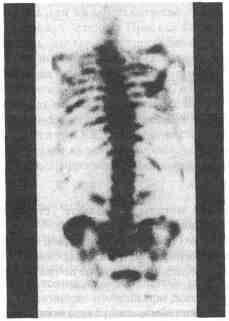

с раком предстательной железы?

Суперсканирование отражает высокую степень окостенения скелета, следствием

которого является интенсивный захват радионуклида костями и отсутствие

его накопления в почках

Исследование кровотока в яичке может помочь при дифференциальном диагнозе перекрута яичка и эпидидимита Сканирование костей обычно применяется при обследовании больных раком предстательной железы и других мочеполовых органов для выявления метастазирования Метайодбензилгуанидин (МЙБГ) дает возможность определить симпатическую активность и помогает при диагностике эктопической феохромоцитомы (рис 8-1) ![]() Рис. 8-1. Метастазы рака предстательной железы при сканировании костей Избранная литература